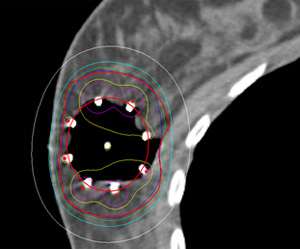

Examples show how the radiation dose (the colored lines, with the white lines representing 50% of the dose) is targeted to the area where the original tumor was using three different partial breast radiation techniques (SAVI, Contura, Tube and Button).

This is in contrast to these examples of standard whole breast radiation where the entire breast is considered the target.

Example of a partial breast case done at UCLA in a woman with breast augmentation who had a SAVI applicator placed. One can see that the distribution of the radiation dose as can be seen in the colored lines is focused around the lumpectomy cavity and that the majority of the implant (light grey) is spared from unnecessary radiation. A different view of the same patient with the SAVI applicator in the lumpectomy cavity just above the implant outlines in yellow.